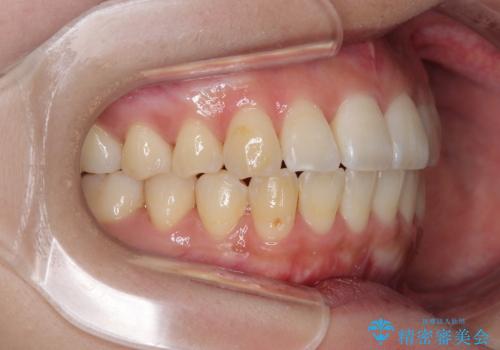

上顎の拡大は、左右どちらに拡大していくのか予想が困難ですが、こちらの患者様では結果として上下正中が一致する方向に拡大され、非常にきれいな仕上がりとなりました。

上顎歯列が下顎の歯列に対して狭小であり、一部下顎の奥歯が上顎よりも外側に位置している状態でした。

上顎の急速拡大装置を使用して上顎骨を側方に拡大することで上顎歯列を拡大し、下顎歯列も拡大できるようにすることで、歯列を整えることとしました。